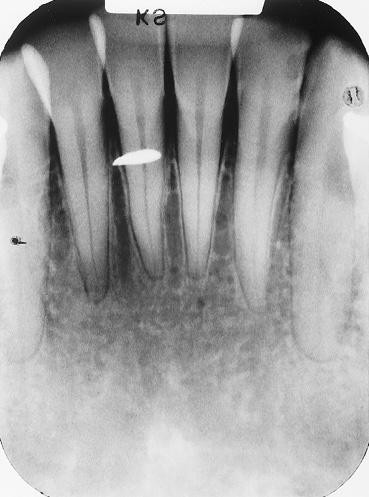

1.  In the X ray bellow for which jaw periodontal bone loss is evident?